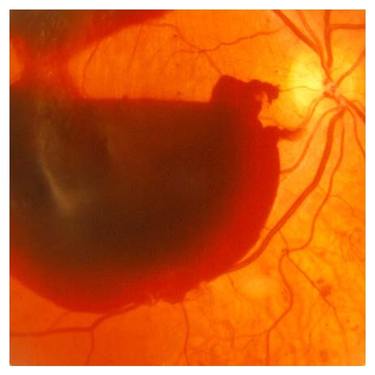

При проблемах с сетчаткой удаление стекловидного тела позволяет получить доступ к зоне поражения и провести необходимые действия с целью восстановления жизнеспособности сетчатой оболочки глаза. Витрэктомия является эффективным методом лечения и при других недугах зрительной системы.

Показаниями к операции могут стать: